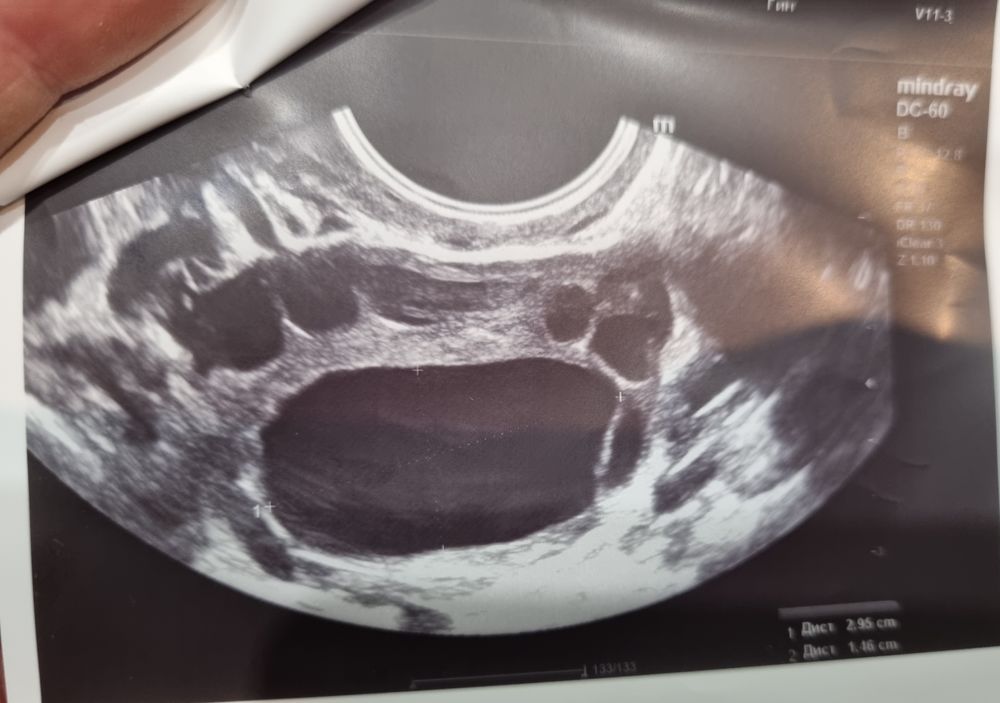

Эндометрий очень неоднородный на 1 фото. 2 фото желтое тело скорее всего. 3 киста фолликулярная. Дюфастон допивайте, на отмене придут месячные. На 5-7 день цикла я бы эндометрий пересмотрела на предмет полипов. Нехорошо выглядит он у вас

Обведен синим эндометрий. Он у вас прям очень неоднородный, похоже, будто месячные вот-вот пойдут